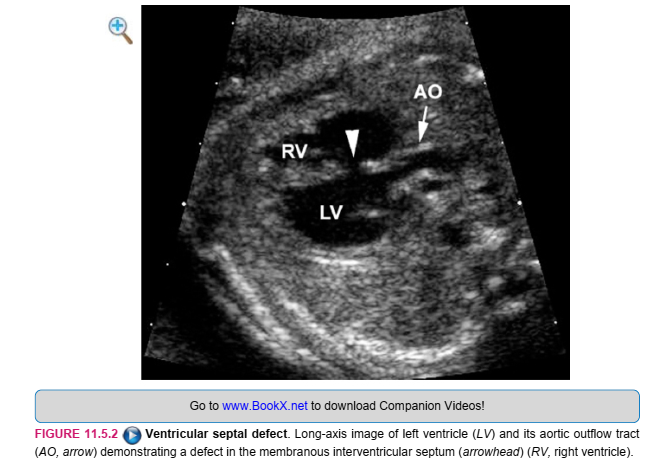

SONOGRAPHY

The diagnosis of a ventricular septal defect is made when a gap is seen in the septum between the right and left ventricles. Many ventricular septal defects can be diagnosed on a four-chamber view of the fetal heart (Figure 11.5.1). Some defects, such as some smaller defects in the membranous portion of the septum, will only be seen on a long-axis view of the left ventricle and left ventricular outflow tract (Figure 11.5.2). Other ventricular septal defects, especially very small membranous ones, may not be visible at all on prenatal ultrasound. Flow across ventricular septal defects in utero, typically from the right to the left ventricle, can be seen with color Doppler imaging (Figure 11.5.3). Because a ventricular septal defect may be a component of a complex cardiac anomaly, careful assessment of ventricular and atrial chamber sizes, atrioventricular valves, ventricular outflow tracts, and the atrial septum is warranted.